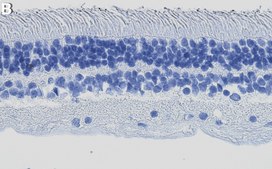

Immunohistochemistry (Paraffin) Analysis: A 1:1,000 dilution from a representative lot detected Arrestin-C in human retina tissue sections.